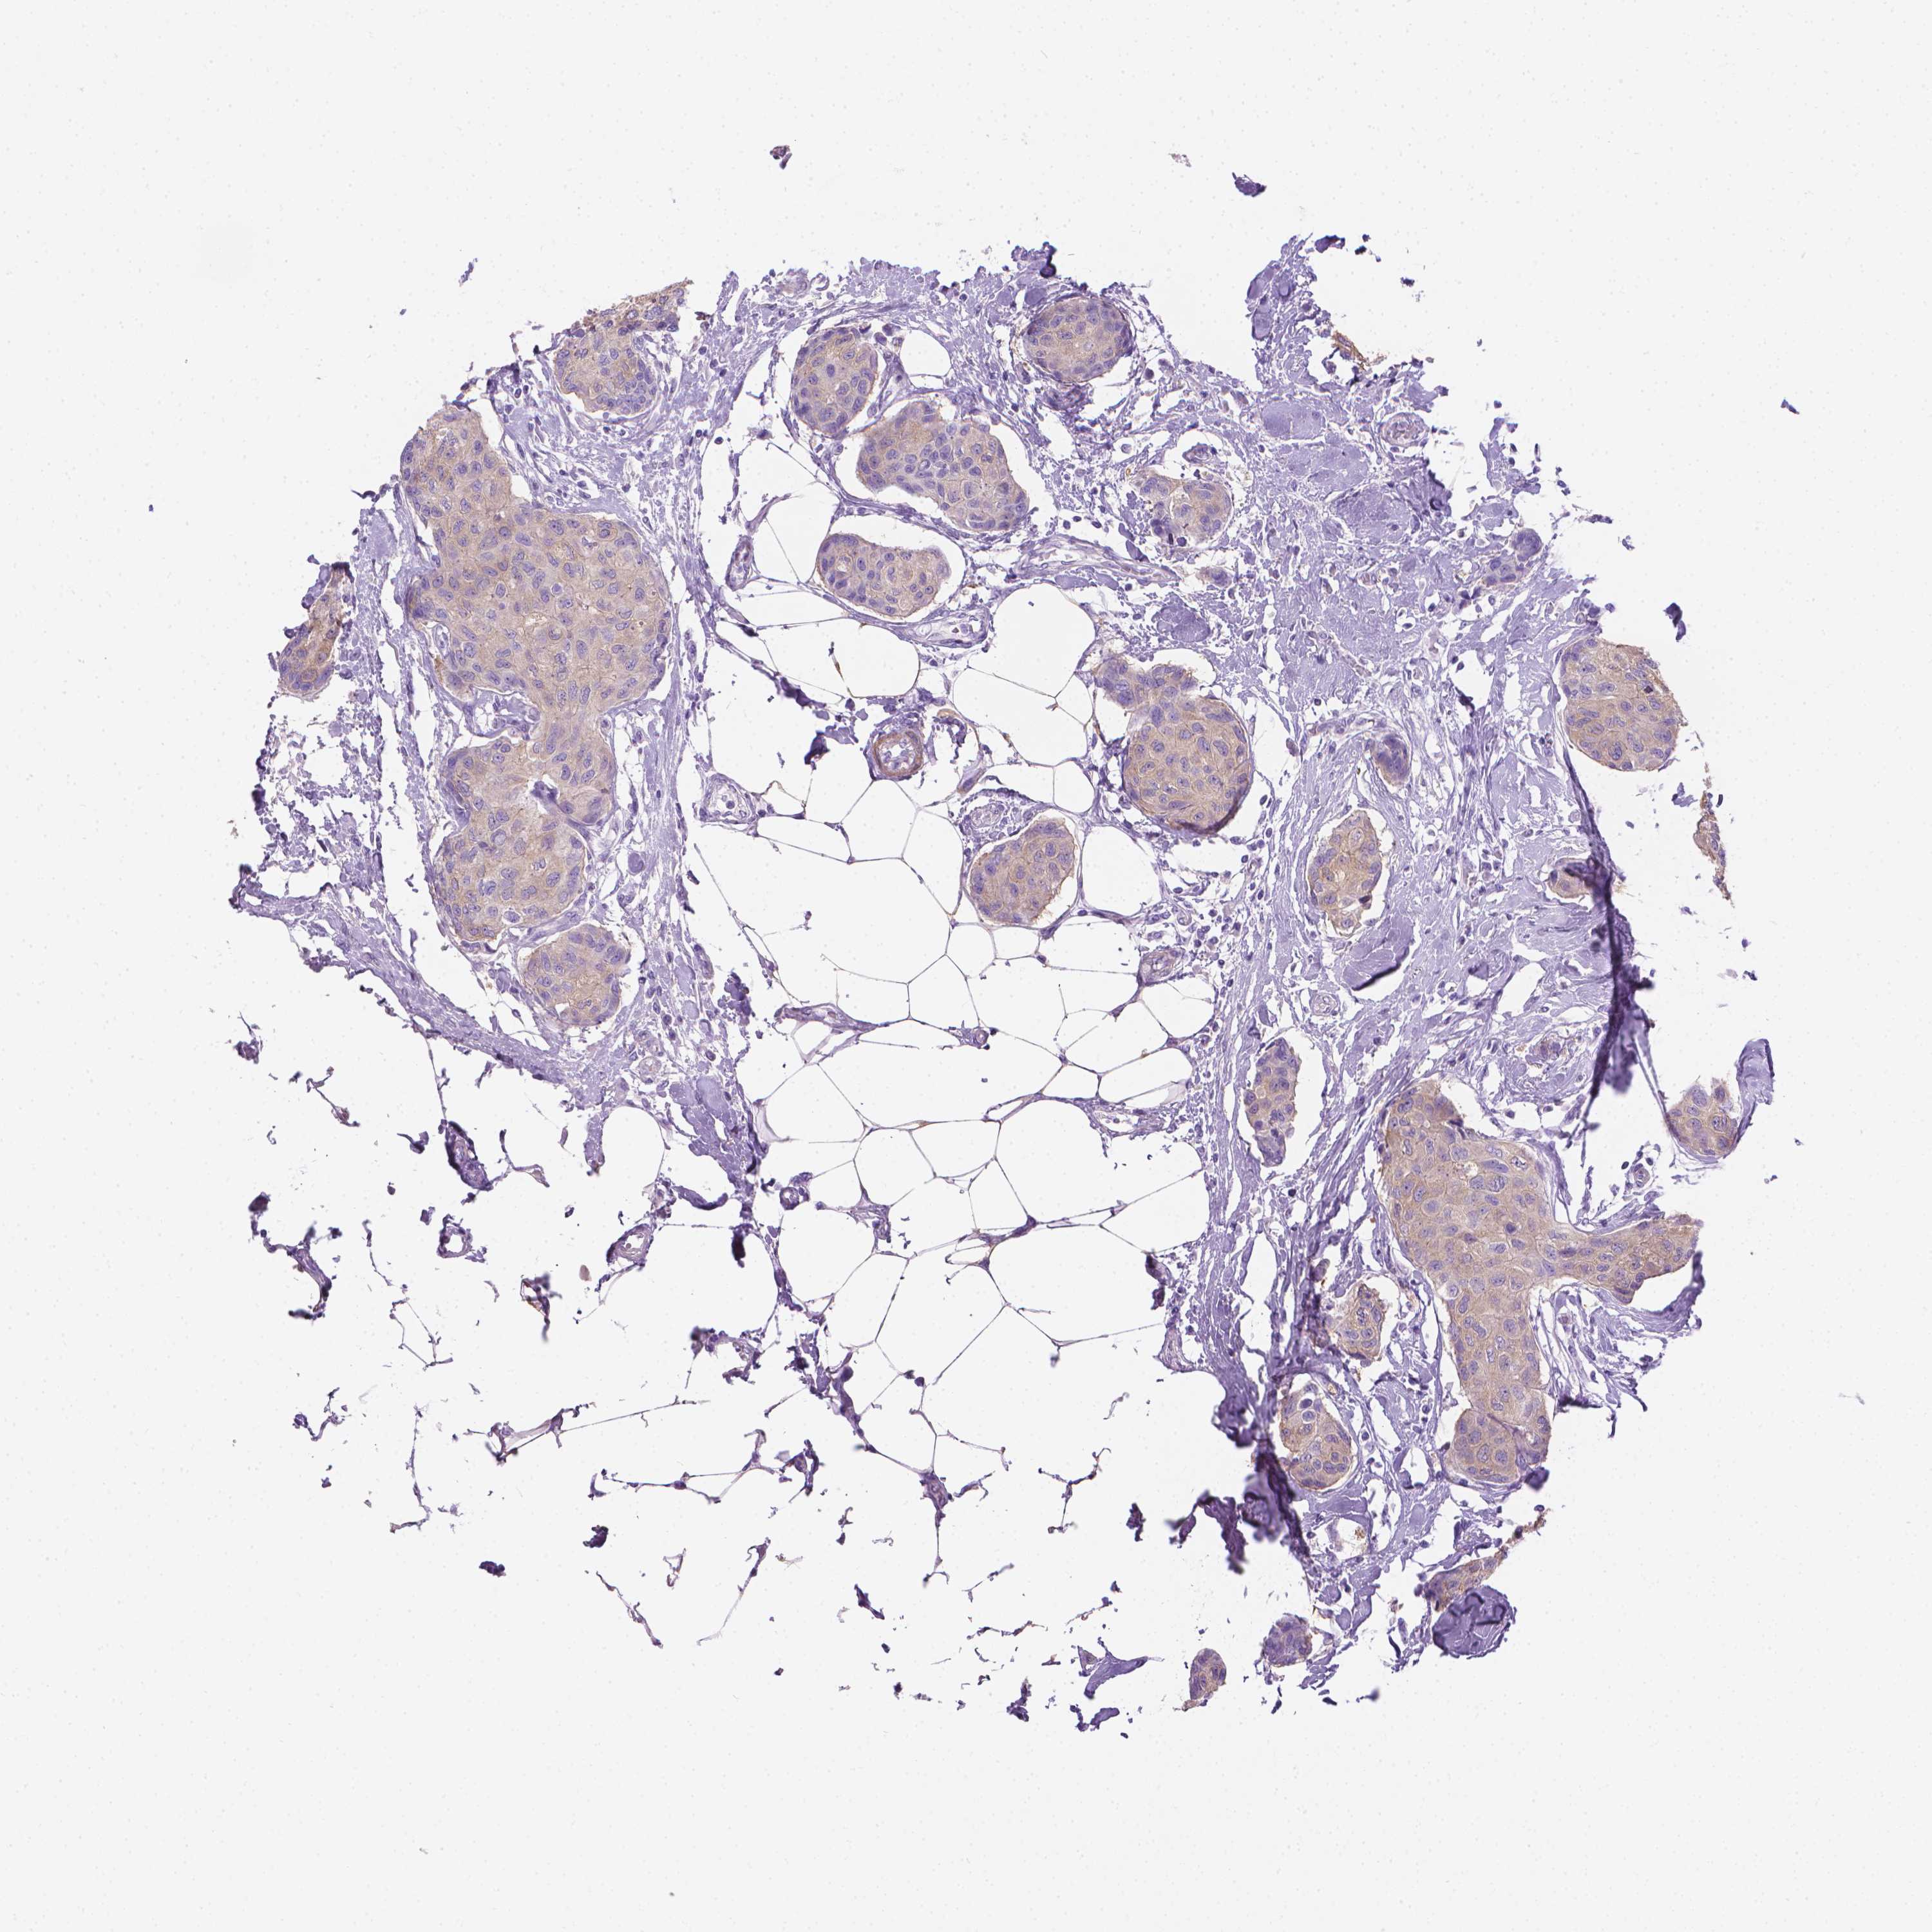

CANCER BREAST CANCER Show tissue menu

BRCA TCGA BRCA VALIDATION PROTEIN EXPRESSION